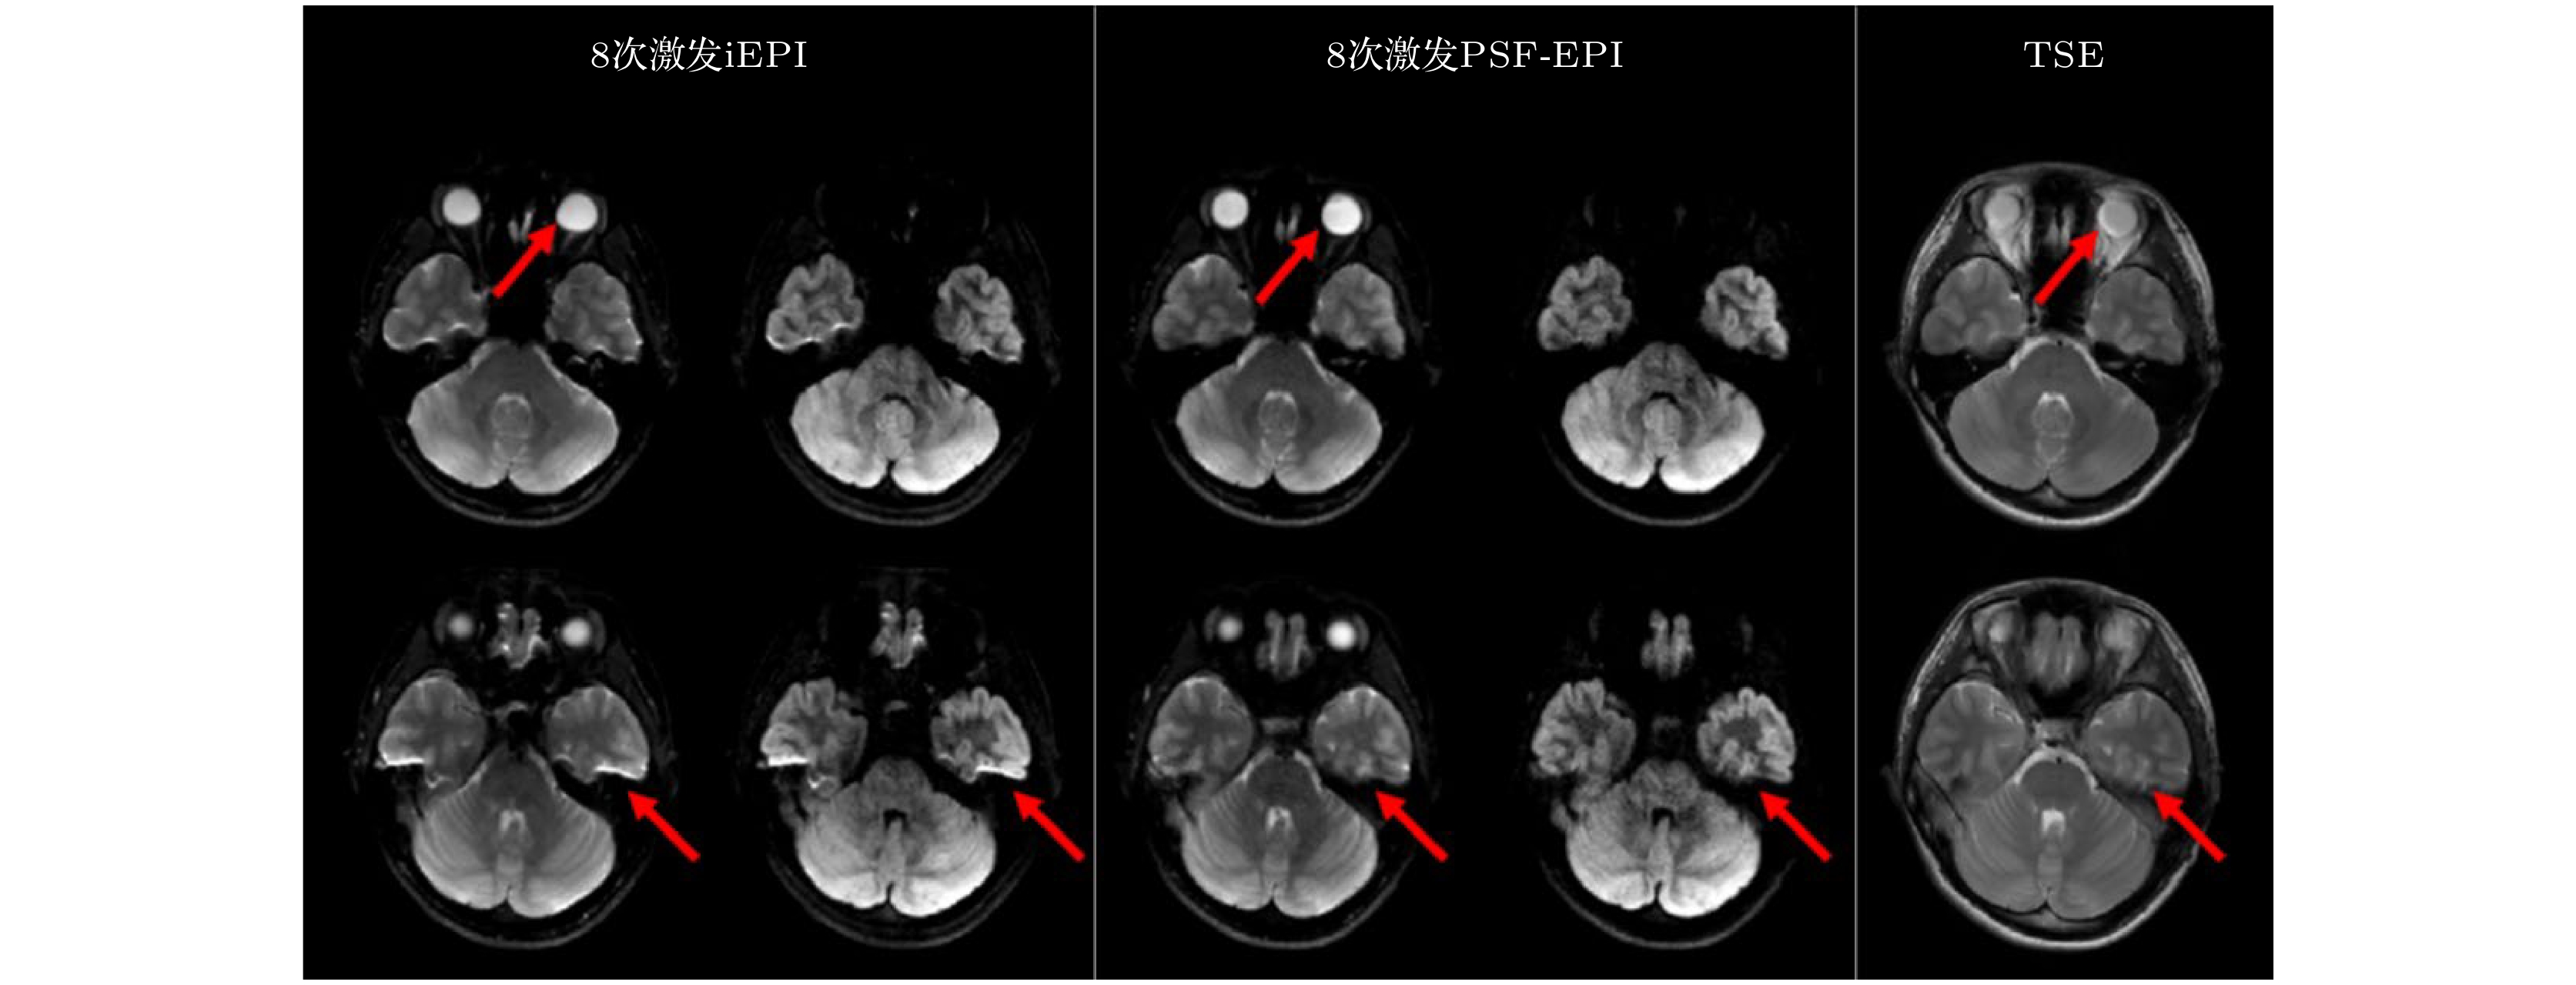

磁共振扩散加权成像(DWI)在神经科学和临床疾病诊断中具有重要价值. 单次激发平面回波成像(ss-EPI)是DWI最常用的技术, 但受主磁场不均匀性和T2/T2*衰减的影响, 易出现几何变形、信噪比低等问题. 为解决这些问题, 研究者开发了更先进的高分辨率磁共振扩散成像技术. 本文对这些成像技术进行综述. 平面回波成像(EPI)方面, 本文介绍了读出分段EPI、交错采集EPI、点扩散函数编码EPI、EPTI等多次激发EPI DWI技术, 这些技术能够减小或消除几何变形、提高图像信噪比和分辨率. 此外, 多次激发EPI与多层同时激发技术(SMS)的结合能够缩短采集时间, 本文对此类技术进行简要介绍. 相较于EPI, spiral成像的信噪比和采样效率更高, 但对主磁场不均匀性更敏感. 在spiral成像部分, 本文分别介绍了单次激发以及多次激发的spiral DWI成像, 以及二者与SMS技术的结合. 本文重点介绍了各类成像技术的原理、采集策略与重建方法. 最后, 本文阐述了高分辨率扩散成像的挑战和未来方向, 包括三维DWI、体部DWI、磁场探针、超强梯度磁共振系统以及超高场磁共振系统.Diffusion-weighted magnetic resonance imaging (DWI) holds significant value in neuroscience and clinical disease diagnosis. The most commonly used single-shot echo-planar imaging (EPI) for DWI is affected by static magnetic field (B0) inhomogeneity and T2/T2* decay, leading to geometric distortion, low signal-to-noise ratio (SNR), etc. To solve these problems, researchers have developed more advanced high-resolution diffusion MRI techniques. This article comprehensively reviews these imaging methods. In the context of echo-planar imaging (EPI), this review covers multi-shot EPI-based DWI techniques, including readout-segmented EPI (RS-EPI), interleaved EPI (iEPI), point spread function-encoded EPI (PSF-EPI), and echo-planar time-resolved imaging (EPTI). These methods effectively reduce or eliminate geometric distortions while improving SNR and spatial resolution. Additionally, the combination of multi-shot EPI with simultaneous multi-slice (SMS) acquisition can shorten scan time, which is also briefly discussed in this article. Compared with EPI, spiral imaging offers higher SNR and sampling efficiency but is more sensitive to B0 inhomogeneity. In the spiral imaging section, we review single-shot spiral DWI and multi-shot spiral DWI, as well as their integration with SMS techniques. This article emphasizes the concepts, acquisition strategies, and reconstruction methods of these imaging techniques. Finally, we discuss the challenges and future directions of high-resolution diffusion imaging, including 3D DWI, body DWI, magnetic field probes, ultra-high gradient systems, and ultra-high-field MRI systems.